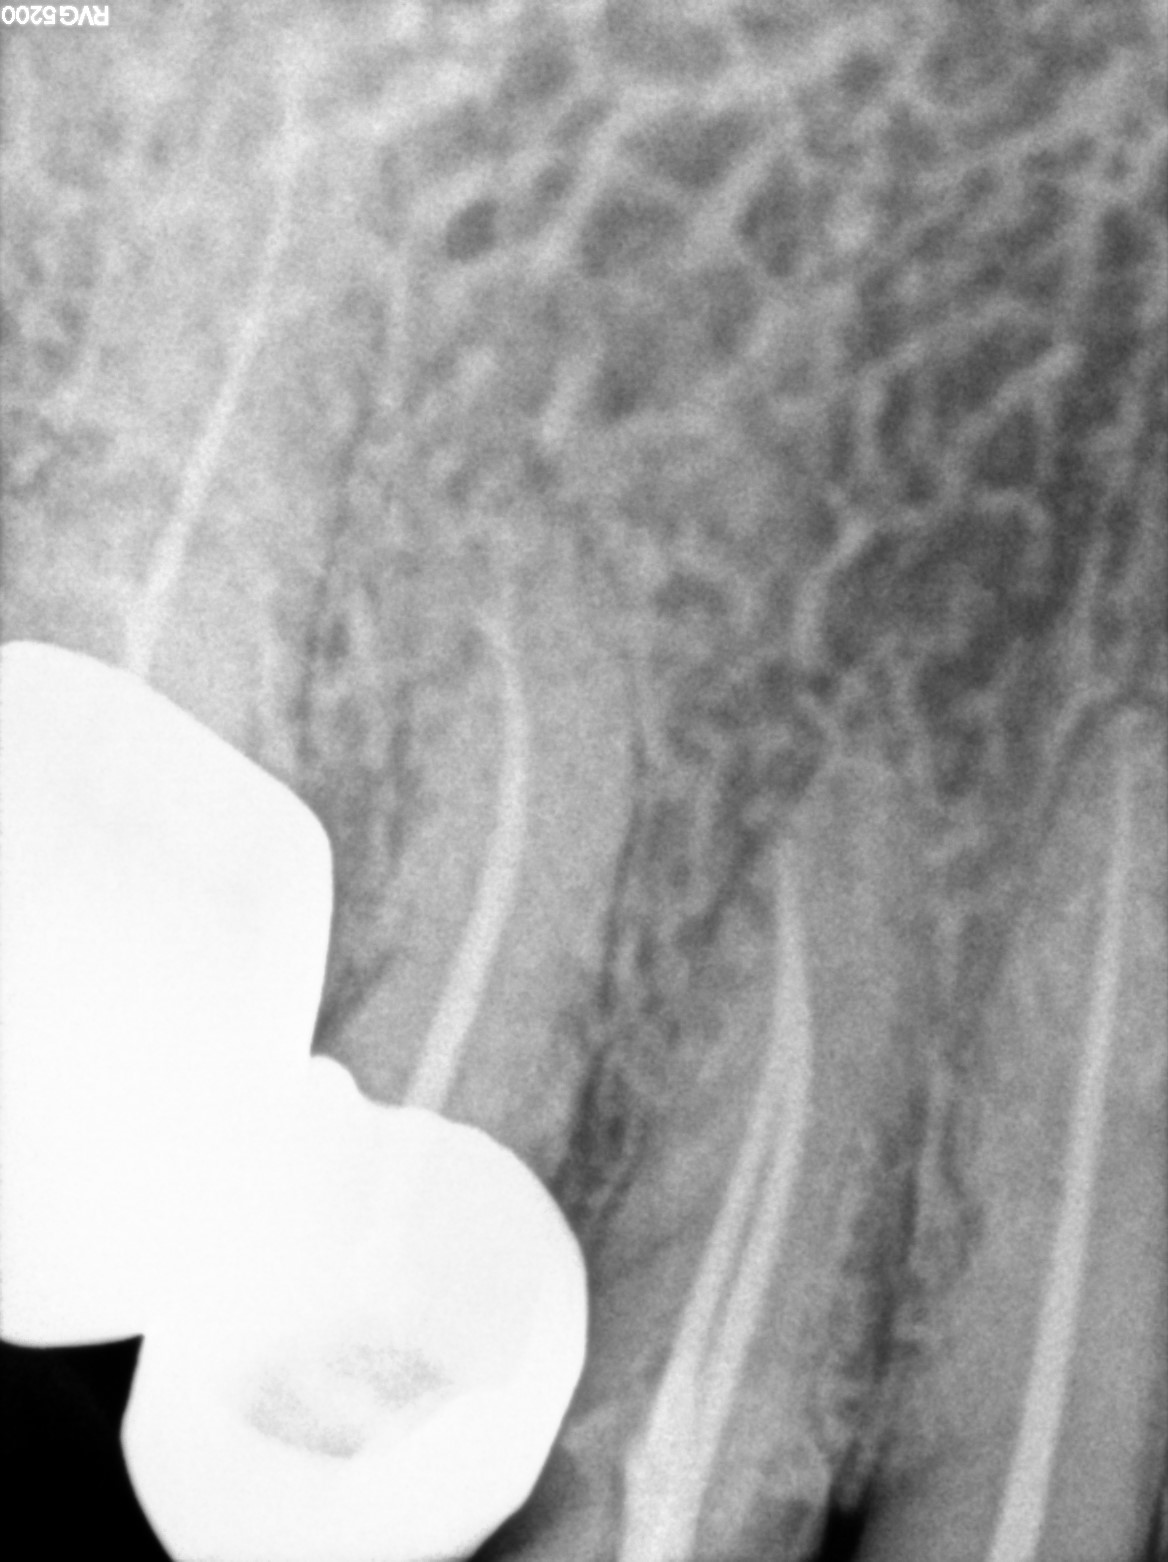

Dental Radiographs FHIR: DocumentReference · LOINC 24641-7

d (1).jpg

24641-7